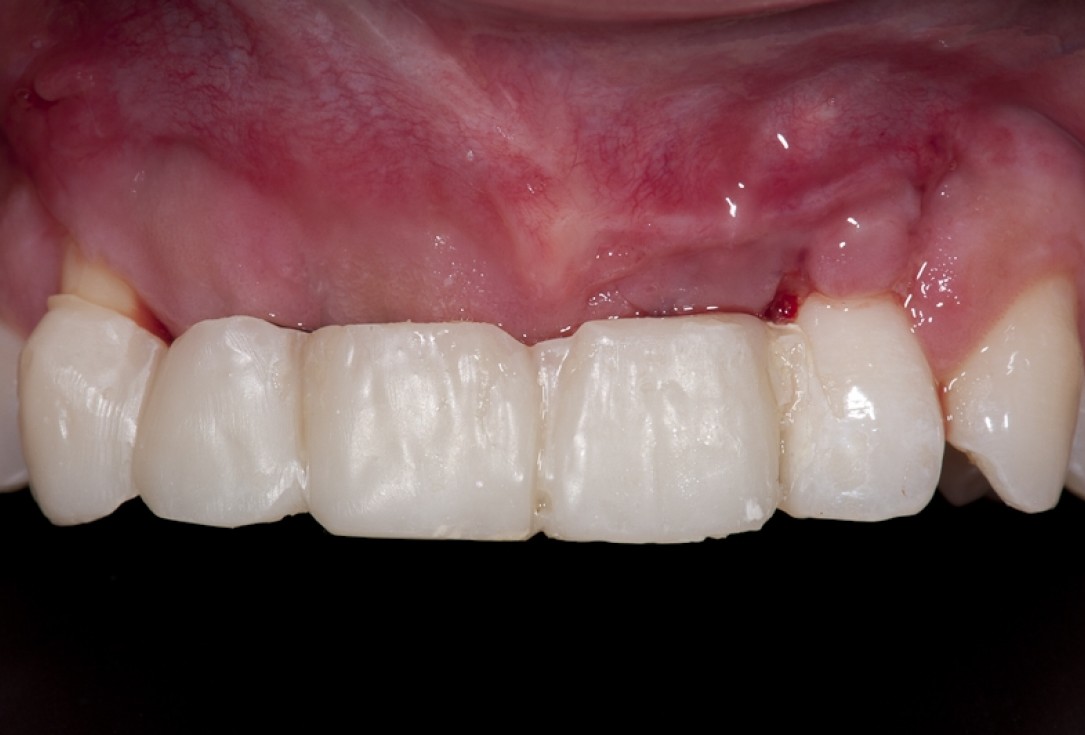

16/17 - Soft tissue situation after temporary prosthesis

17/17 - Final denture with nice papilla